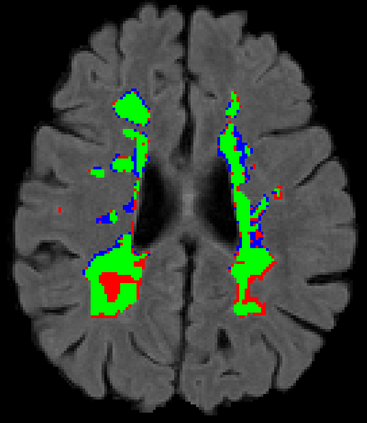

Recently, segmentation methods based on Convolutional Neural Networks (CNNs) showed promising performance in automatic Multiple Sclerosis (MS) lesions segmentation. These techniques have even outperformed human experts in controlled evaluation conditions such as Longitudinal MS Lesion Segmentation Challenge (ISBI Challenge). However state-of-the-art approaches trained to perform well on highly-controlled datasets fail to generalize on clinical data from unseen datasets. Instead of proposing another improvement of the segmentation accuracy, we propose a novel method robust to domain shift and performing well on unseen datasets, called DeepLesionBrain (DLB). This generalization property results from three main contributions. First, DLB is based on a large group of compact 3D CNNs. This spatially distributed strategy ensures a robust prediction despite the risk of generalization failure of some individual networks. Second, DLB includes a new image quality data augmentation to reduce dependency to training data specificity (e.g., acquisition protocol). Finally, to learn a more generalizable representation of MS lesions, we propose a hierarchical specialization learning (HSL). HSL is performed by pre-training a generic network over the whole brain, before using its weights as initialization to locally specialized networks. By this end, DLB learns both generic features extracted at global image level and specific features extracted at local image level. DLB generalization was validated in cross-dataset experiments on MSSEG'16, ISBI challenge, and in-house datasets. During experiments, DLB showed higher segmentation accuracy, better segmentation consistency and greater generalization performance compared to state-of-the-art methods. Therefore, DLB offers a robust framework well-suited for clinical practice.